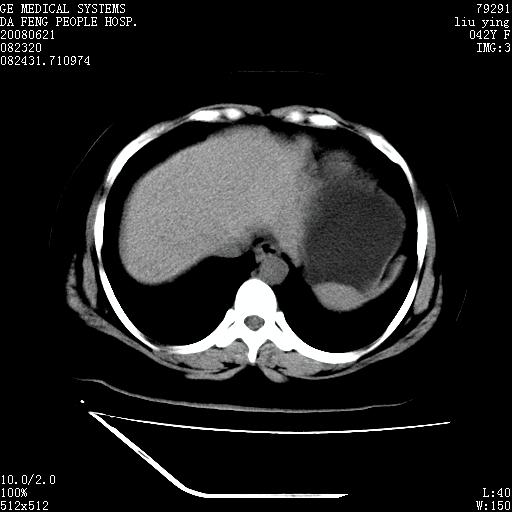

标题: CT14225:女性46岁。当地B超示肝内占位,来我院作CT检查。请 [打印本页]

标题: CT14225:女性46岁。当地B超示肝内占位,来我院作CT检查。请

速升速降,支持肝癌.脾体积增大,形态欠规整,请询问病史是否做过脾动脉栓塞.

速升速降,支持肝癌可能。

快进快出,符合肝癌表现-----------

肝内结节强化特点符合原发性肝癌表现,脾脏改变考虑为增大及先天发育所致。

动脉期病原灶明显强化高于肝密度且中央有无强化区,静脉期强化程度下降明显,延迟低于肝密度,考虑肝腺瘤可能性大,

肝内结节强化特点:快进快出符合原发性肝癌表现

此患者虽然符合快进的特点,却不符合快出的特点,因为门脉期几乎是等密度,不符合肝癌的增强表现,所以我考虑肝局灶性结节增生可能性大